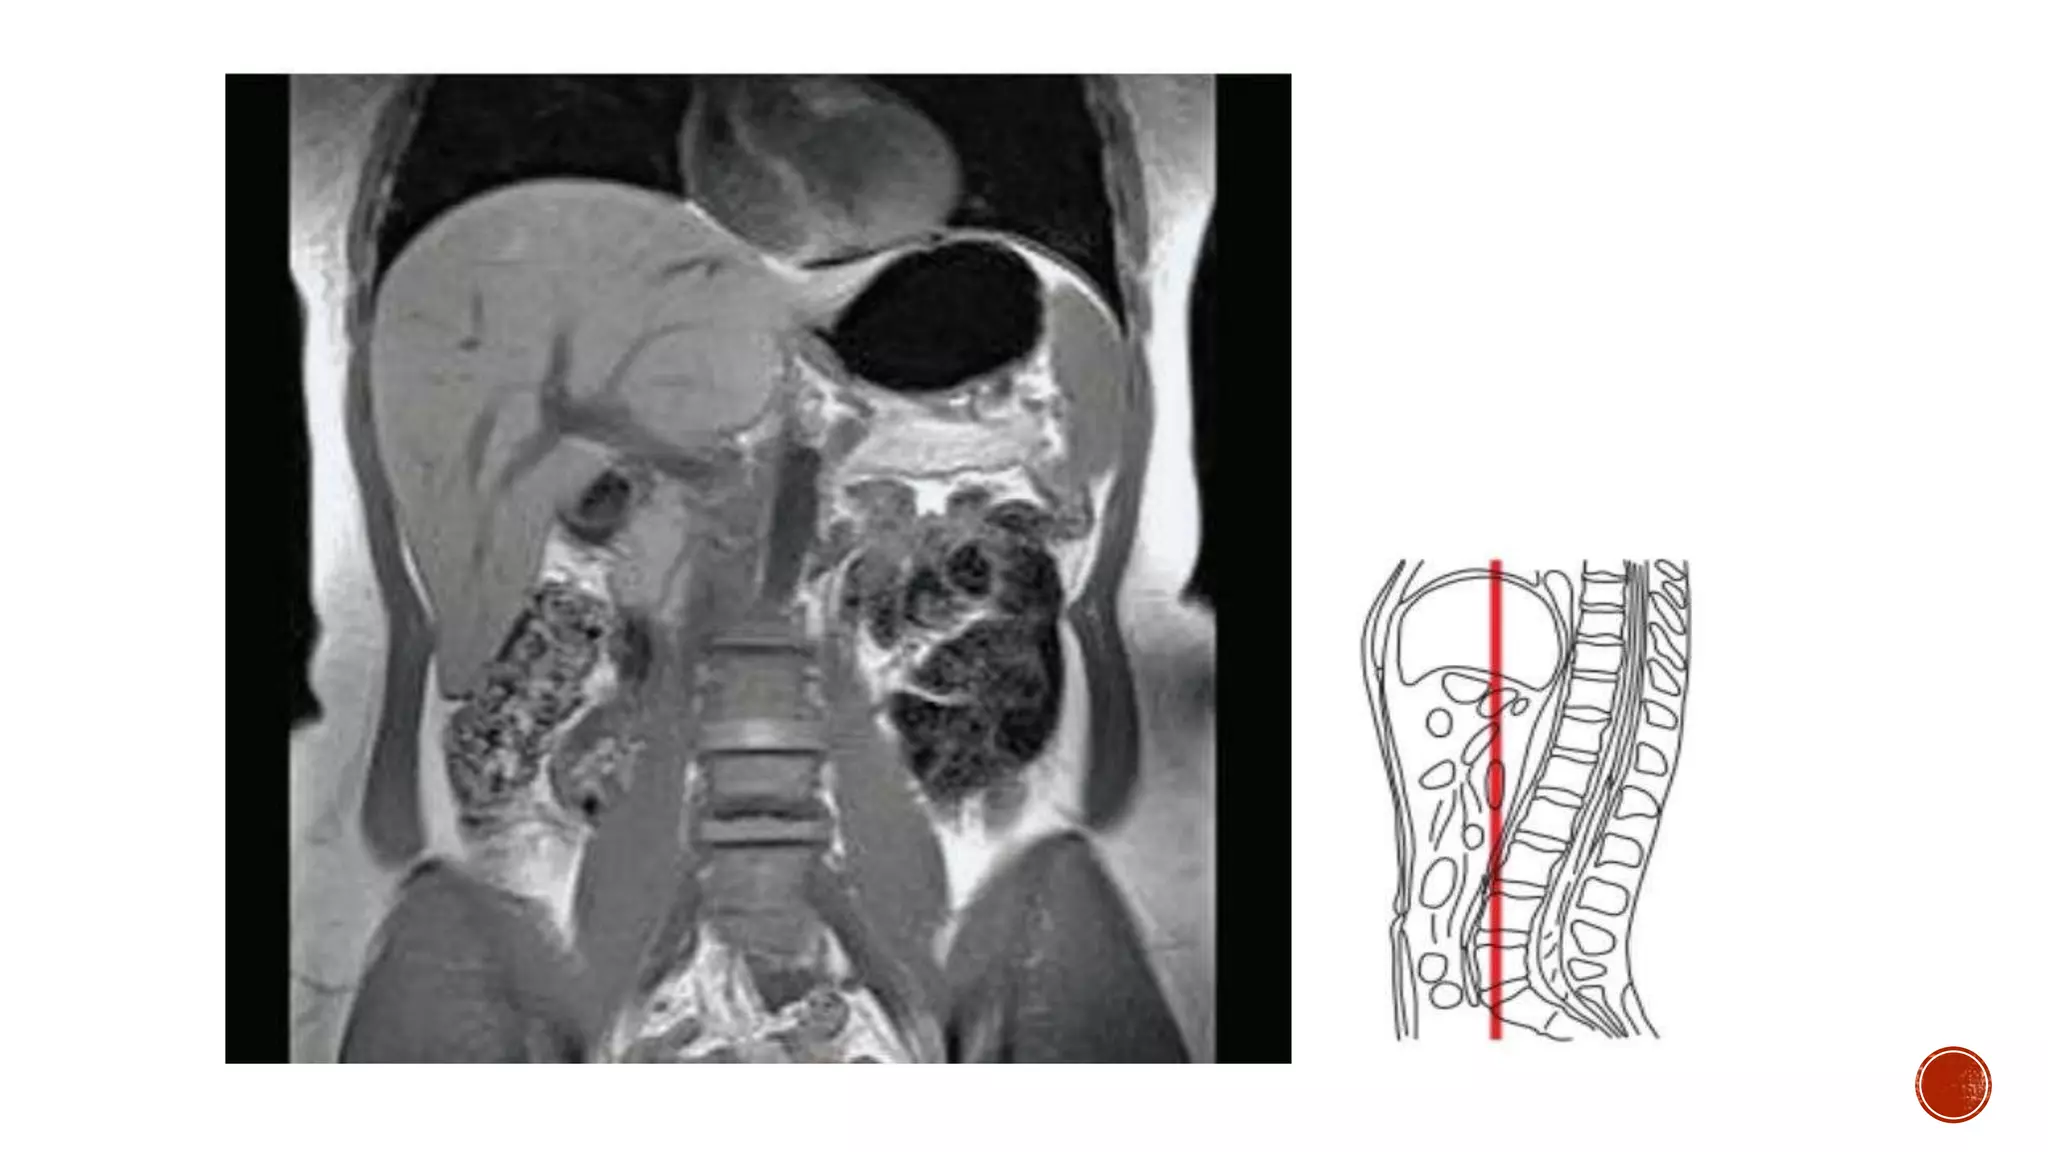

The document describes the anatomy of the abdomen and pelvis region of the human body. It lists over 40 structures and their locations, including major organs like the liver, kidneys, intestines, blood vessels and muscles of the abdominal wall and pelvis. The structures are grouped into sections focusing on different anatomical areas like the abdomen, retroperitoneum, pelvis and gluteal region.